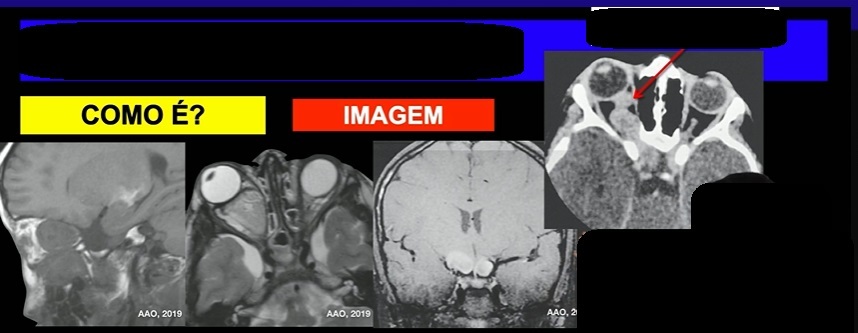

o que é?

qual diag?